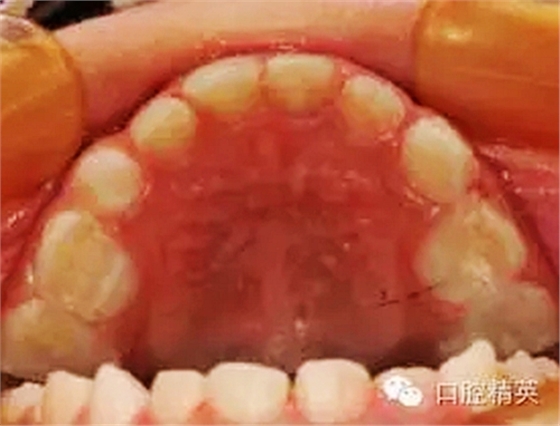

臨床檢查:頜面部及頸部未見明顯異常??谇恍l(wèi)生狀況尚可, 52,61,62,63,73唇舌面齲,54,64,74,84牙合面齲壞,腐質(zhì)中等,叩(-),松(-),牙齦未見明顯異常;75牙合面深齲壞,大量軟腐,叩(-),松(-),牙齦未見明顯異常,腐質(zhì)未去凈見露髓孔;51大面積齲壞,大量腐質(zhì),叩(+),松(Ⅰ),唇側(cè)牙齦可見5mm×6mm的包,軟;余牙未見異常。

①52,61,62,63,73,54,64,74,84去腐備洞,氫氧化鈣墊底,全酸蝕,DE-BOND加3M樹脂充填,調(diào)合,磨光。

②75,51局麻下開髓、拔髓,根管預備,生理鹽水沖洗,Vitapex根充,鋅汀墊底,全酸蝕,DE-BOND加3M樹脂充填,調(diào)合,磨光。